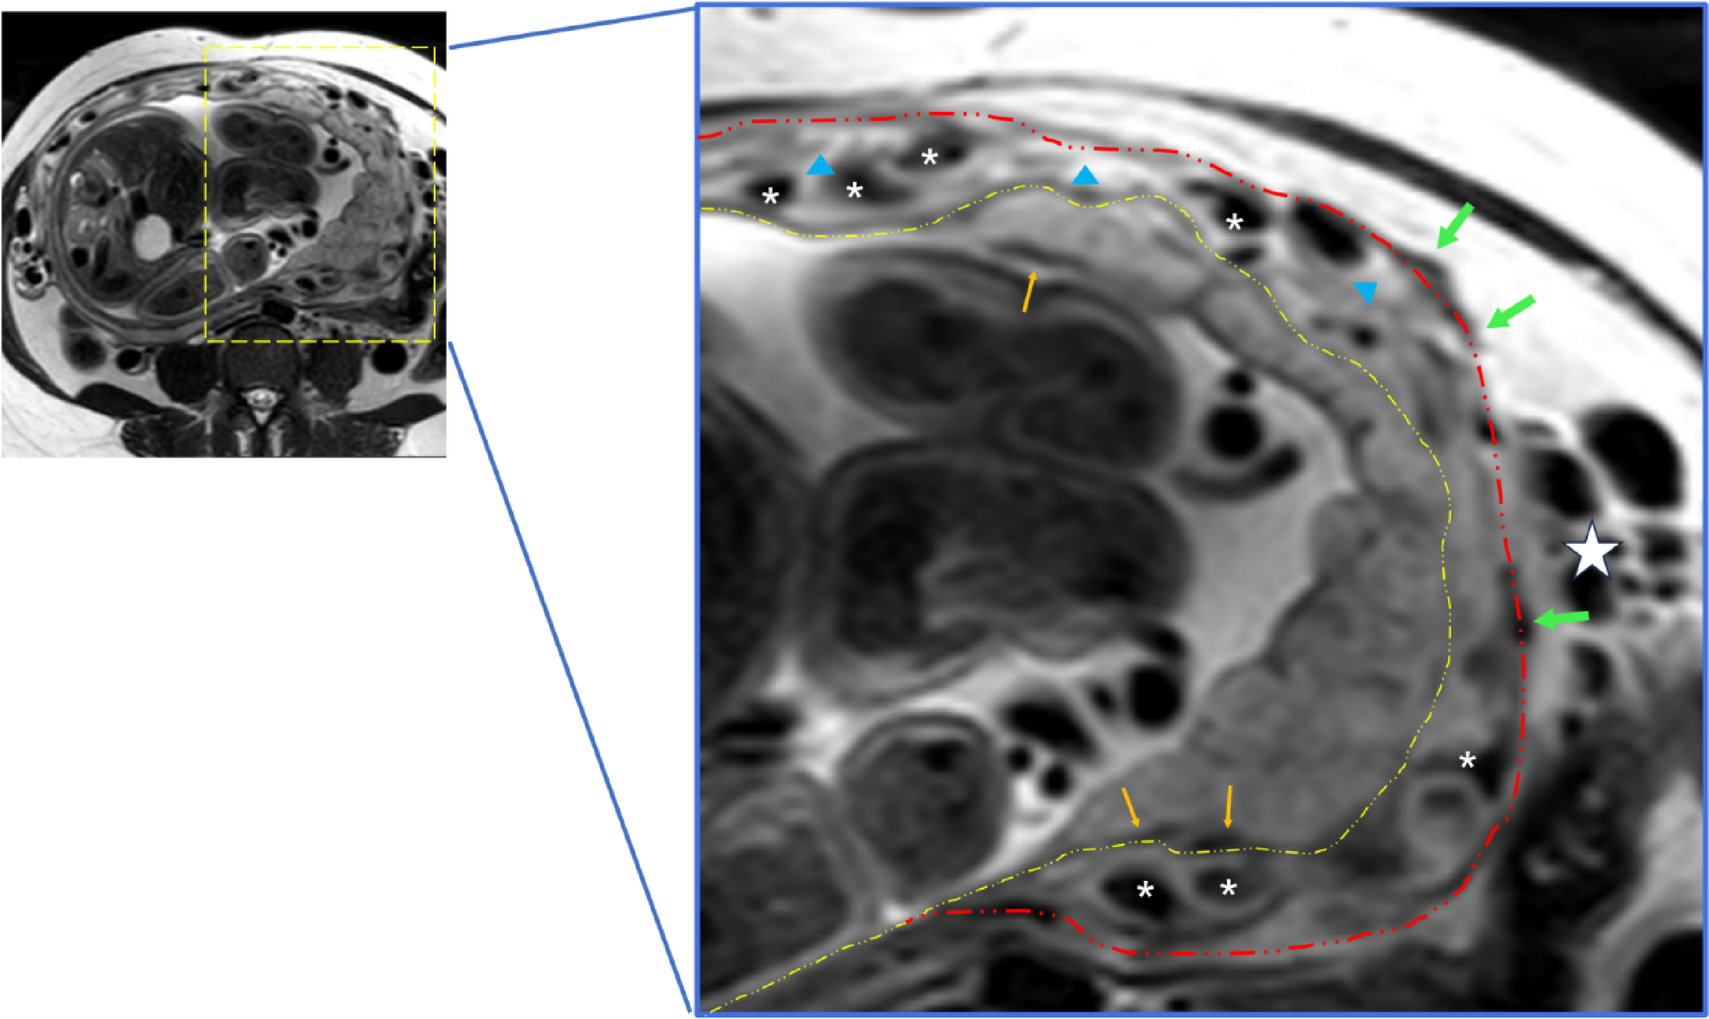

Fig. 4

The key differences between the Novel Sign and abnormal vascularization of the placental bed. The enhanced vascularization confined within the myometrium can be observed, which are distinct from the placental bed and parametrial vessels. White asterisks: the novel sign ‘increased intra-myometrial vascularity’ appears as continuous tubular or tortuous flow-void structures within the myometrium. Myometrium with hypertrophy, indicated by blue triangles, exhibits higher T2 signal intensity compared to myometrium without hypertrophy. Orange arrows: bed vascularization. Green arrows: serosa vascularization. Yellow dashed line: placenta-utero interface. Red dashed line: serosa side.